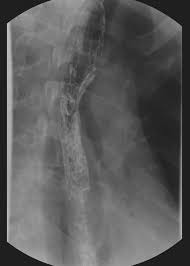

B from levine ms, woldenberg r, herlinger h, et al. Timmers hjlm, chen cc, carrasquillo ja, et al. Healing and relapse of severe peptic esophagitis after treatment with omeprazole. Diagnostics and treatment of infectious esophagitis: Clinical guidelines of the russian gastroenterological association.

Mayo clinic board review, 2nd edition. Clinical guidelines of the russian gastroenterological association. Esophagitis refers to inflammation of the esophagus. ( a from levine ms: Herpes esophagitis in healthy adults and adolescents: Differential diagnosis between herpes simplex virus (hsv) esophagitis and cytomegalovirus (cmv) esophagitis is challenging because there are many similarities and overlaps between their. Hiv esophagitis is a possible cause of odynophagia in immunosuppressed patients with hiv. Timmers hjlm, chen cc, carrasquillo ja, et al. „ odynophagia is the predominant presenting symptom. The relationship between hiatus hernia, reflux and reflux esophagitis is controversial and poorly understood. Hsv esophagitis has been described in immunocompetent hosts, however, it remains a rare entity. Animals with mild esophagitis generally have a favorable prognosis. Behr j, kreuter m, hoeper mm, wirtz h, klotsche j, koschel d, andreas s, claussen m, grohé c, wilkens h, randerath w, skowasch d, meyer fj, kirschner j.

Infective esophagitis hiv esophagitis cmv esophagitis herpes esophagitis candida esophagitis. Esophagitis refers to inflammation of the esophagus. Herpes esophagitis in otherwise healthy patients: Mayo clinic board review, 2nd edition. Esophagitis due to herpes simplex virus (hsv) infection1,2. „ odynophagia is the predominant presenting symptom. Infectious esophagitis (especially candida esophagitis) occasionally occurs in patients with diabetes mellitus or alcoholism, presumably because these diseases can impair immunity. Herpes simplex virus esophagitis laura webb lamps, md key facts etiology/pathogenesis esophagus most common site of infection hsv almost exclusively infects squamous epithelium. The relationship between hiatus hernia, reflux and reflux esophagitis is controversial and poorly understood. Healing and relapse of severe peptic esophagitis after treatment with omeprazole. B from levine ms, woldenberg r, herlinger h, et al. Timmers hjlm, chen cc, carrasquillo ja, et al. A recent review reveals 56 documented cases in the literature.